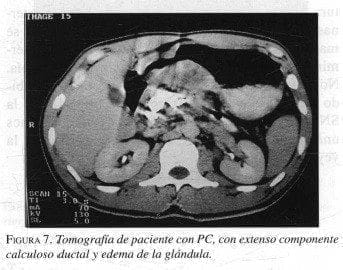

La evaluación con imágenes en la PC permite delimitar el compromiso de la glándula y las estructuras en vecindad, el estudio imagenológico preferido es la TAC (figuras 7 y 8). El ultrasonido, la resonancia magnética y el mismo ultrasonido endoscópico (16) pueden ofrecer datos complementarios, pero en general no son imprescindibles. Sin embargo, la colangiopancreatografía endoscópica retrógrada (CPER) frecuentemente puede cambiar la elección de la técnica operatoria. La colangiorresonancia brinda importante información en lo referente a la presencia o no de una masa inflamatoria o neoplásica en la cabeza, dilatación del conducto de wirsung, estenosis dominantes, presencia de cálculos en el Wirsung, seudoquistes, obstrucción del duodeno o del colédoco o complicaciones vasculares peripancreáticas como la trombosis de la esplénica con várices gástricas, hipertensión mesentérica o seudoaneurismas de las arterias intra o peripancreáticas. Las mayores expectativas están en la colangiorresonancia para reemplazar la CPER como estudio menos invasivo, con la limitante del intervencionismo que brinda la CPER (litotricia, extracción de cálculos, colocación de “stent”) (17).